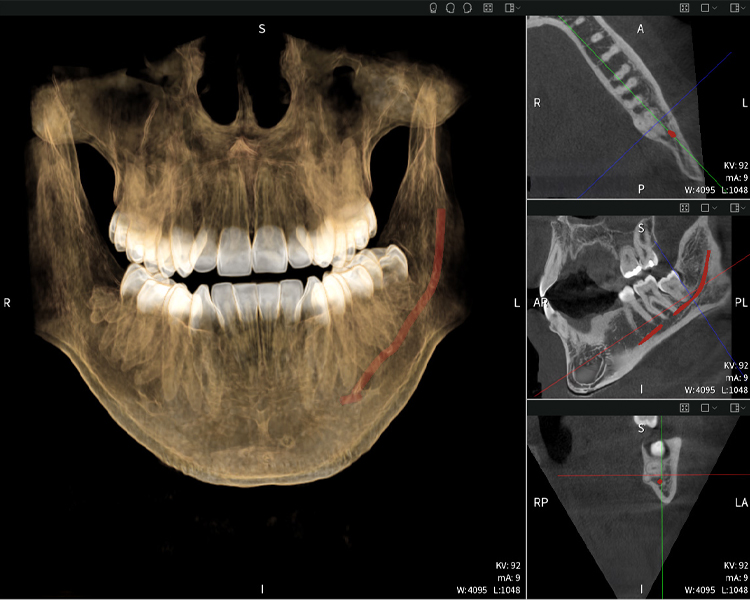

Nachstehend finden Sie einen Fall von Dr. med. dent. Oliver A. Centrella, in dem die CBCT-Aufnahmen mit Seethrough Max entscheidende Informationen zur komplexen Anatomie sowie zur kritischen Beziehung zwischen den Weisheitszähnen und dem Nervus alveolaris inferior lieferten. Bei diesem Fall besteht eine Indikation zur chirurgischen Entfernung der Weisheitszähne.

Abbildungen b–d zeigen verschiedene Ansichten einer 3D-Rekonstruktion des Unterkiefers und bieten eine umfassende Übersicht über die Anatomie des Unterkiefers, die Lage der Nerven im Verhältnis zu den Zähnen und ermöglichen die Beurteilung der Zahnsymmetrie und Ausrichtung.

Abbildung d zeigt den bereits vorbehandelte Zahn 48, dessen Krone entfernt wurde und dessen Wurzeln nahe am Nerv belassen wurden, was das hohe Risiko einer Nervenschädigung verdeutlicht.